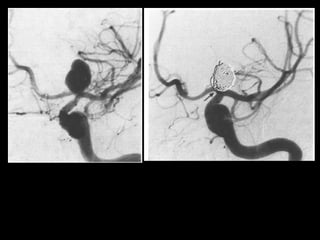

-2D frontal view following vertebral

artery injection , shows normal

intracranial vertebral basilar

circulation , note the blush (*) of the

choroid plexus

1 vertebral artery

2 posterior inferior cerebellar artery

(PICA)

2v vermian branch of PICA

2h hemispheric branch of PICA

3 basilar artery

4 anterior inferior cerebellar artery

(AICA)

5 superior cerebellar artery (SCA)

5h hemispheric branch of SCA

5v vermian branch of SCA

6 posterior cerebral artery (PCA)

6.2 P2 segment of PCA

8 posterior temporal branch of PCA

9 parieto-occipital branch of PCA

10 calcarine branch of PCA

12 posterior thalamoperforating arteries

13L lateral posterior choroidal artery

16 pontine perforating artery

* blush of choroids plexus